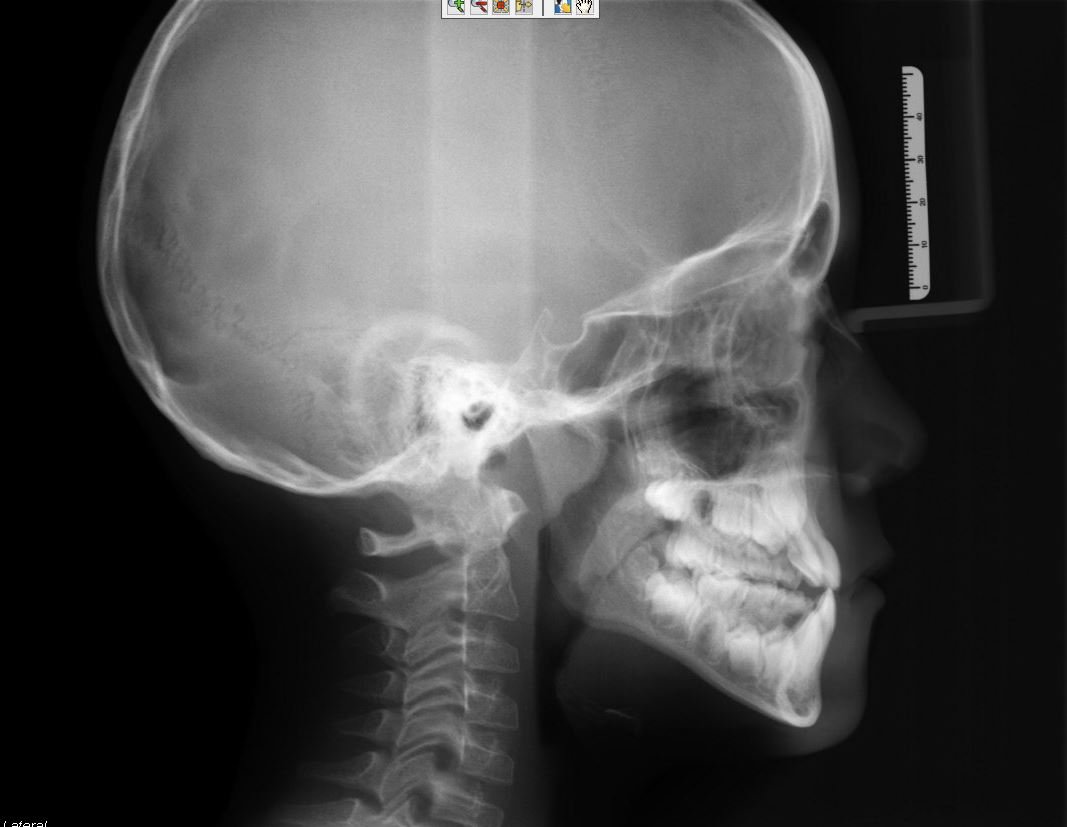

ceph class 2 retrognathic.JPG